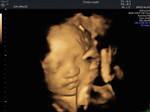

แม่ท้อง

Kim cươngแม่ท้อง